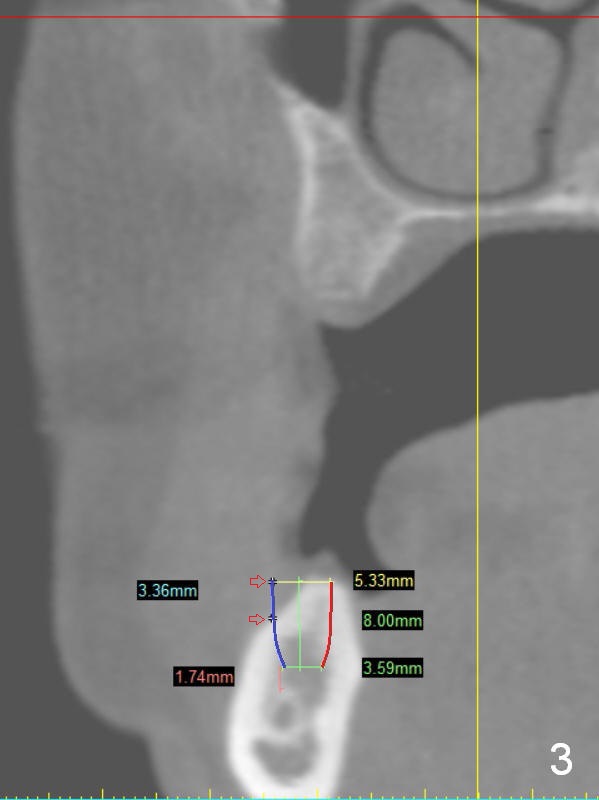

A 49-year-old lady is petit. An implant is placed at #3 and ready for restoration. The crest at #30 is narrow (Fig.1 ^). Bone density at the cortex, around the Inferior Alveolar Canal (IAC) and the medulla is D1, D2 and D3, respectively. It appears that a 10 mm bone-level implant is too close to IAC (Fig.2), whereas a 8 mm one has enough clearance (Fig.3,4). With the same diameter, there will be less thread exposure if the implant is placed a little lingually (Fig.4 (between arrows), as compared to Fig.3).

Since the patient is small and the cortex is dense, a 4.5x8.5 mm UF implant should meet masticatory force as long as #14 and 19 also receive implants. Her mouth should be small. Consider using sensor 1.舌侧骨板厚,适当磨去,让植体舌侧移动。